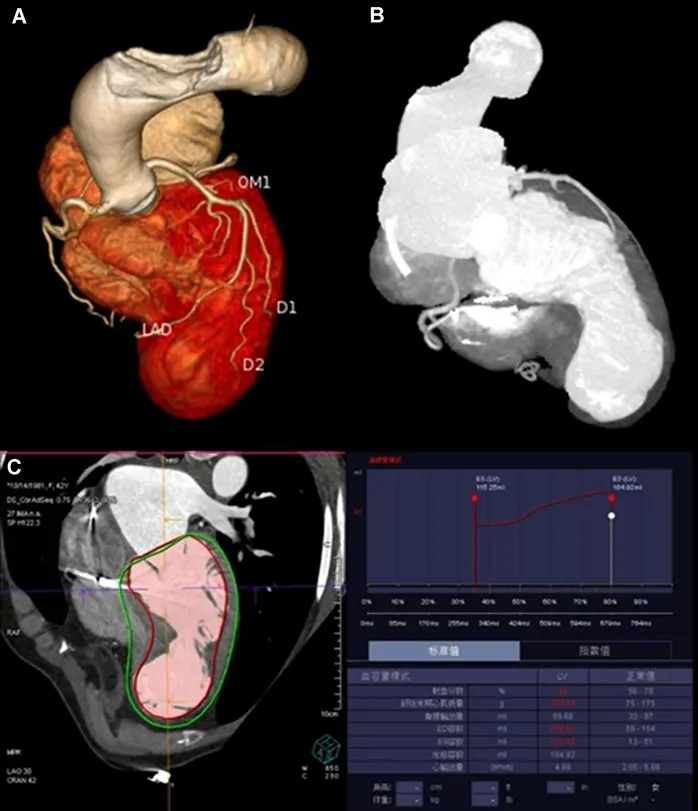

经胸超声心动图提示:巨大解剖性心尖部室壁瘤,约占左心室容积60%,伴收缩期反常运动(图1);室间隔呈代偿性肥厚,而左心室中段及基底段收缩正常。负荷成像提示:重度人工瓣膜狭窄(峰值流速4.4 m/s,峰值与平均跨瓣压差分别为74 mmHg与41 mmHg),中度二尖瓣反流,左心室射血分数减低(25%)。CTA提示:前壁心尖部存在巨大室壁瘤(图3A、3B);左心室舒张末期容积为184 mL,收缩末期容积为119 mL,射血分数为38%(图3C)。动态心电图监测显示:窦性心律与起搏心律并存,多形性室性早搏,完全性右束支传导阻滞,以及短阵室性心动过速;心室异位激动灶可能起源于前乳头肌根部。

图3 CTA检查

图注:(A及B)心尖前壁可见巨大解剖性室壁瘤。(C)左心室舒张末期容积为184 mL,收缩末期容积为119 mL,射血分数为38%。